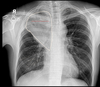

que patrón pulmonar es

A

consolidación